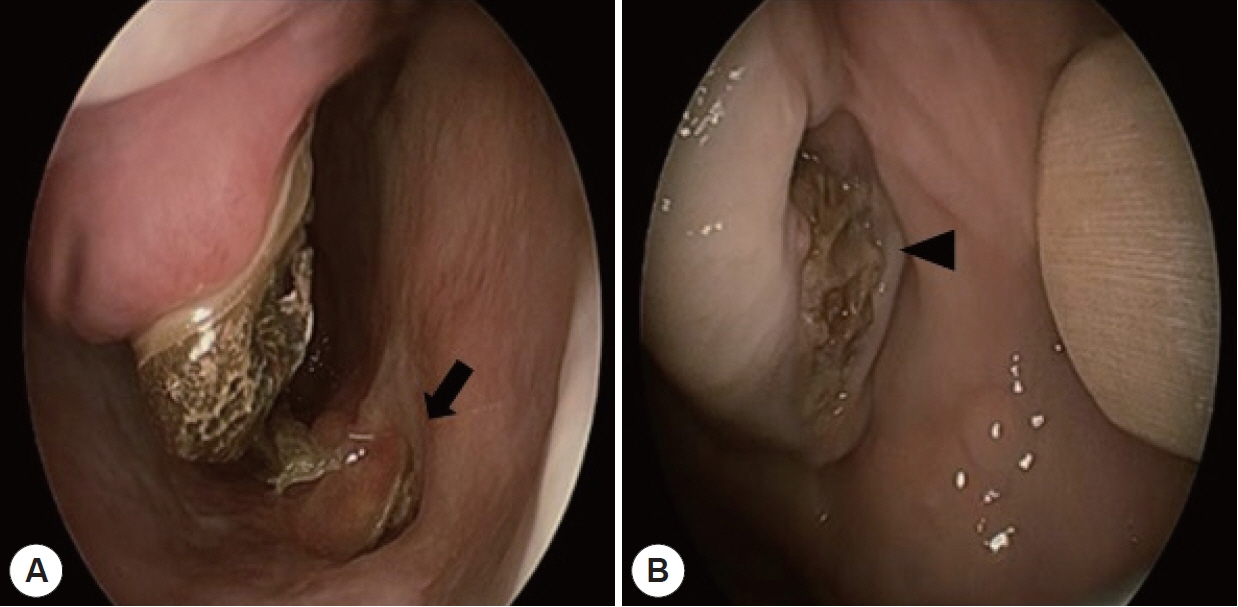

- Central skull base osteomyelitis (CSBO) is a rare, fatal condition seen mostly in elderly diabetic or immunocompromised patients; it mainly involves the sphenoid or occipital bones and diagnosis is often delayed. A 72-year-old male with diabetes was referred to our department with severe pain in the maxillary gingiva. Endoscopic biopsy of the pterygoid bone confirmed the presence of mucormycosis combined with Klebsiella pneumoniae infection. Sinus surgery was performed with bilateral alveolar bone sequestrectomy. Long-term intravenous broad-spectrum antibiotic therapy using meropenem and ampicillin/sulbactam and antifungal therapy using amphotericin B (100 mg/day) was administered; an oral antifungal agent, posaconazole (800 mg/day), was also prescribed for 11 weeks. At the 6-month follow-up visit, there were no complications and no progression of the CSBO lesion was observed. Timely diagnosis and multidisciplinary treatment including endoscopic surgery, alveolar bone sequestrectomy, and combined antifungal and antibiotic therapy can reduce mortality and minimize complications associated with CSBO.

Figure